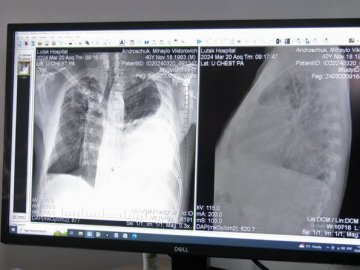

Щодня у рентген-кабінеті центру проходять обстеження орієнтовно 60 людей. Як зазначила завідувачка відділення Валентина Мостова, сюди направляють пацієнтів з підозрою на туберкульоз.

"Це туберкульоз в легенях і великий плеврит лівобічний ексудативний плеврит, тобто, набирається рідина в плевральній порожнині. Він до нас поступає на лікування, лікується і виписується майже здоровим", — сказала лікарка.